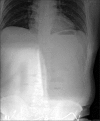

The most common cause of small-bowel obstructions in adults is postoperative adhesions. However, strangulation of the small intestine in a patient without history of laparotomy is a rare condition. We experienced an unusual case of a small-bowel obstruction secondary to omental encasement in a patient without previous history of abdominal surgery or acute inflammatory process in the abdomen.